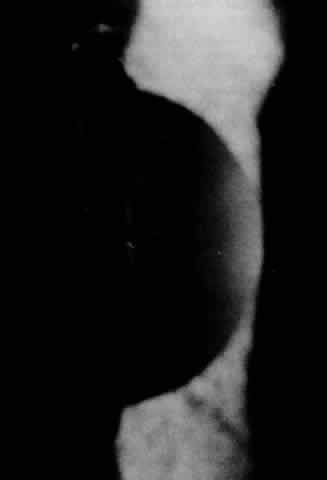

Corneal changes (Fig. 8) are usually noted within the first decade of life and consist initially as a diffuse, bilaterally symmetric anterior stromal clouding. Later, cloudy gray-white macular opacities appear. Unlike granular dystrophy, the “maculae” occur in all parts of the cornea and no peripheral or intervening clear zone is found. Additionally, corneal thinning is a typical finding in this dystrophy, serving to differentiate it from other stromal dystrophies in which pachymetry is usually normal.112–114 With time, increased opacification of the cornea occurs with spread of the cloudy gray-white lesions peripherally, anteriorly, and posteriorly. Through the increasingly dense background fog, focal white aggregates are found and tend to be larger in the anterior axial cornea. Some of these superficial deposits may cause focal elevation of the epithelium, but epithelial erosions are uncommon. Descemet's membrane later appears hazy, and endothelial guttata are seen.37,74

Fig. 8. Macular dystrophy: multiple gray-white ground glasslike haze in the intervening stroma.